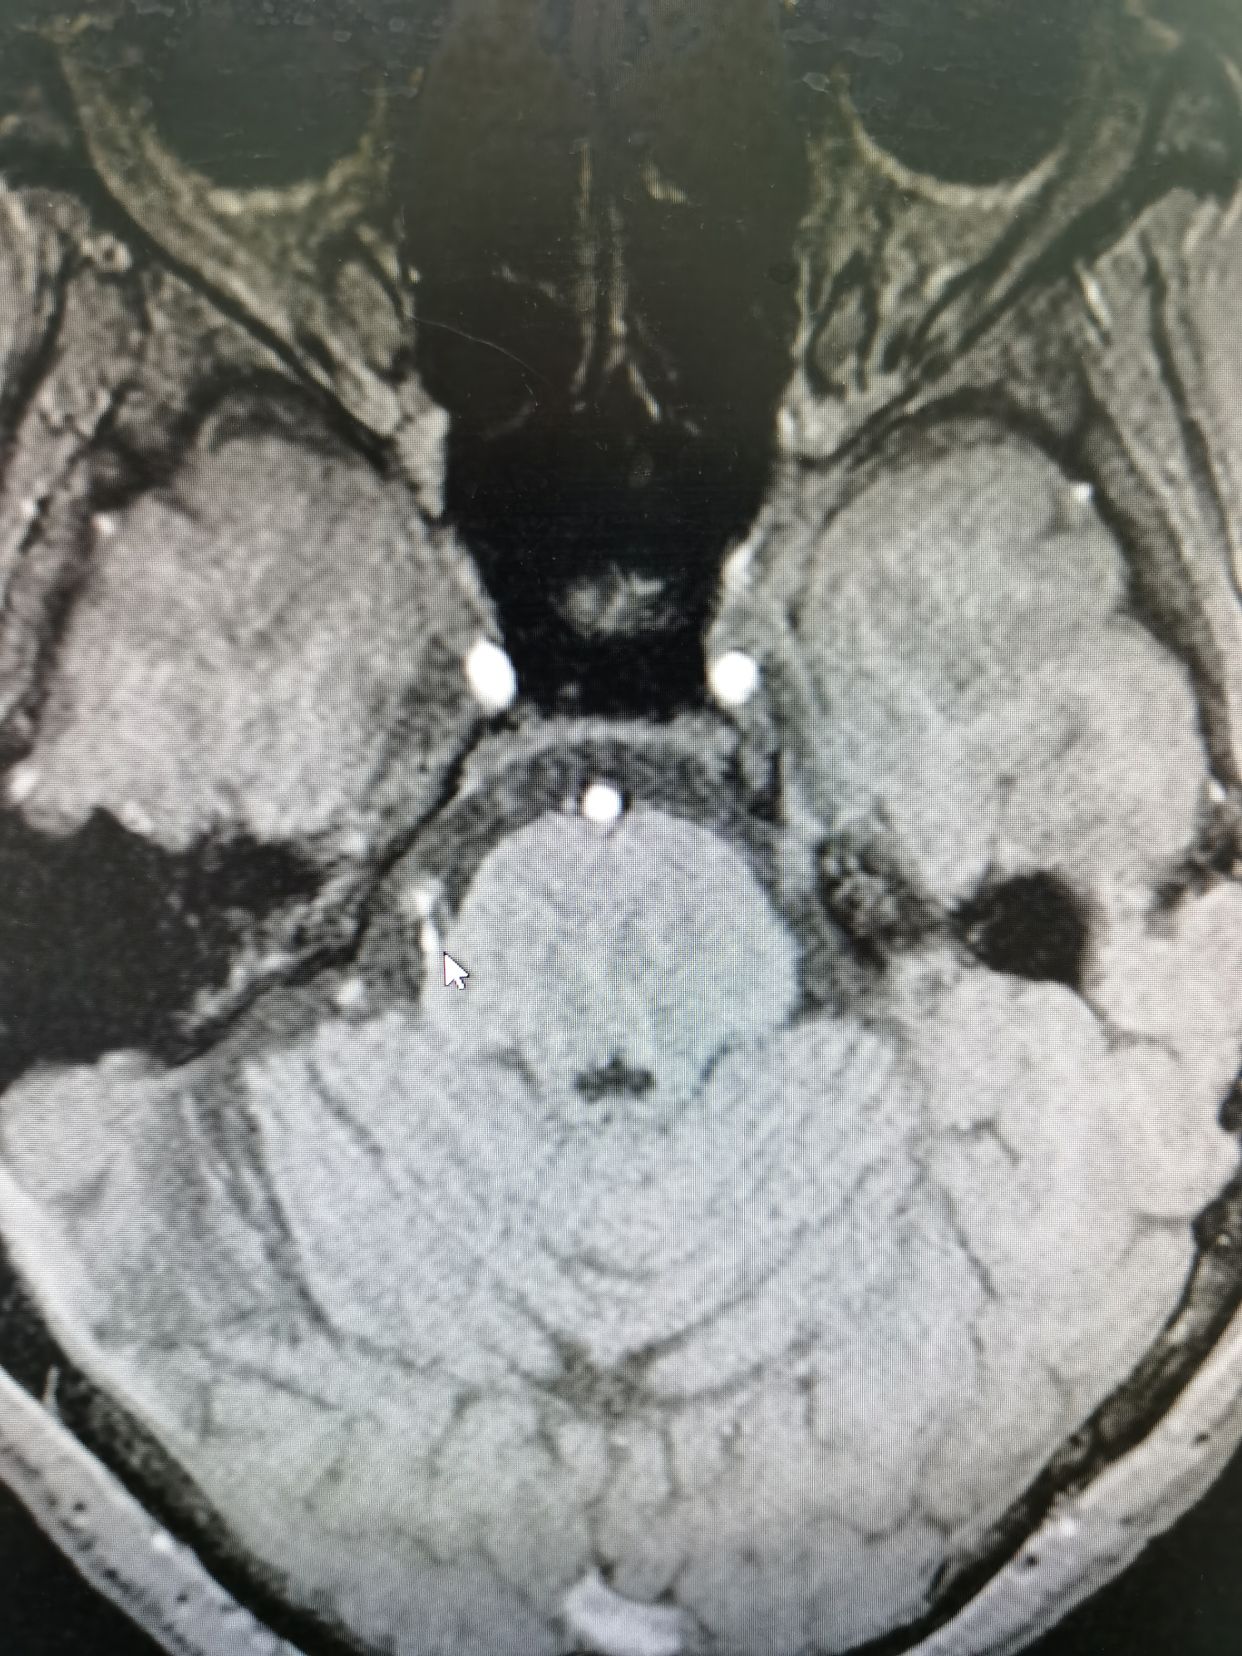

老年女性,右面部疼痛2年,鼻翼外侧为扳机点,目前口服卡马西平已经效果不好,于全麻下行神经内镜下微血管减压术。

右侧SCA从腹侧压迫三叉神经

全程彻底减压